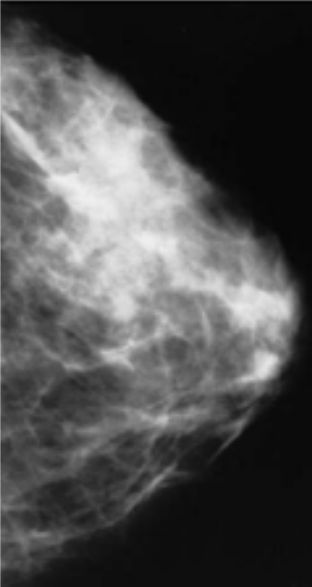

Mammography or MRI?

3D mammography, also known as digital breast tomosynthesis (DBT), allows a clearer visualisation of the tissue when compared to the traditional 2D mammography and is becoming increasingly common. Guidelines recommend either 2D or 3D mammography for patients with average risk of breast cancer.

Breast MRI is recommended by the American Cancer Society yearly only for patients with 20% to 25% lifetime risk of cancer. These patients should begin early MRI and mammograms at the age of 30.